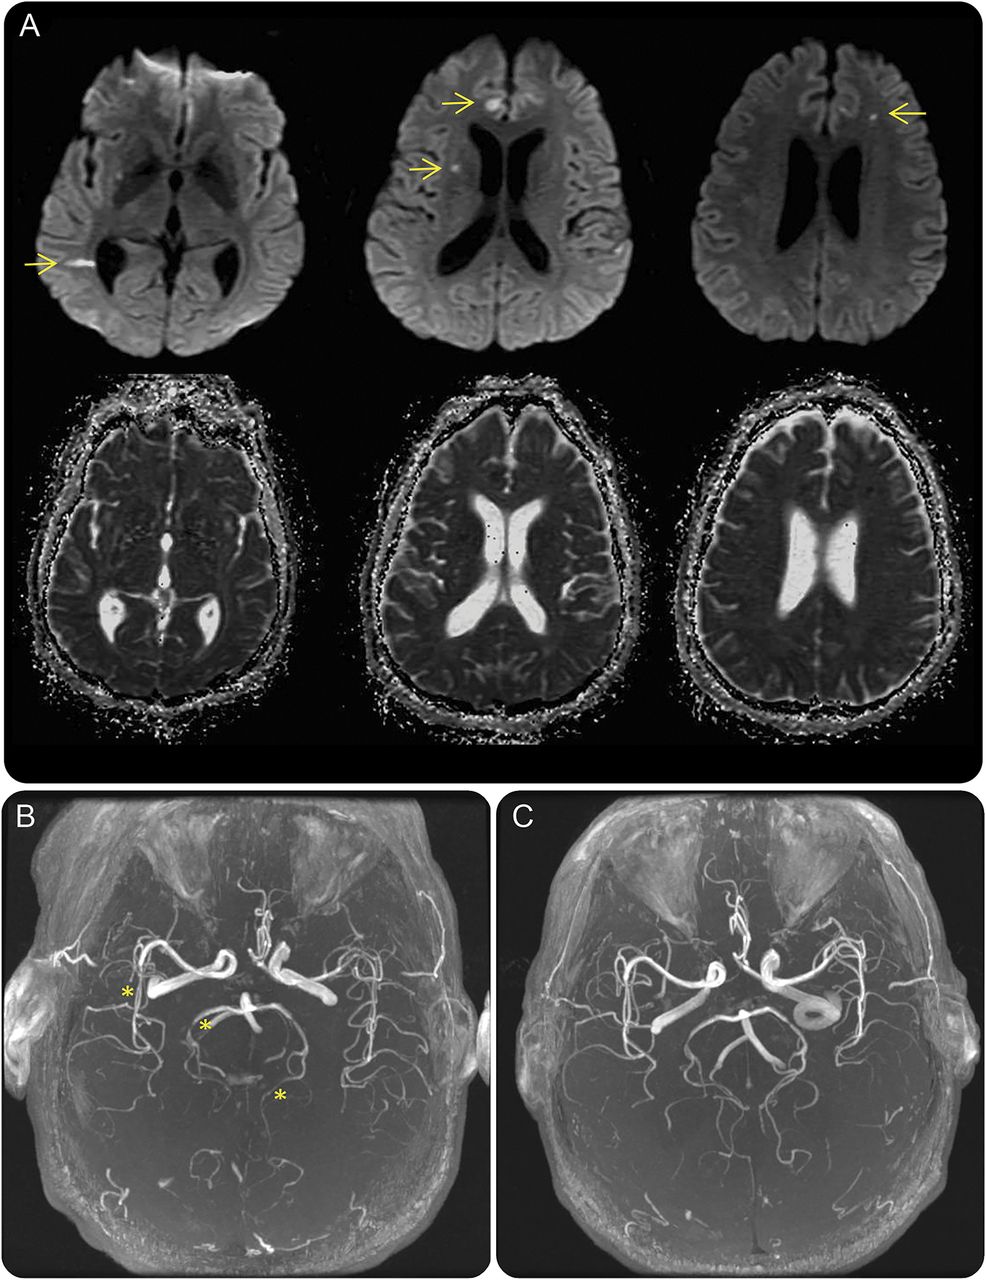

(A)轴向diffusion-weighted(上面一行)头部MRI显示限制扩散在多个血管领土(箭头),包括两国前脑动脉的分布,对大脑中动脉和大脑后动脉。领域的扩散限制显示相应hypointensity表观扩散系数成像(底下一行),与急性缺血性梗塞一致。(B)头部MRA显示两国后腔的不规则性脑动脉和右大脑中动脉的分支(星号),符合血管炎。(C)重复10天的抗真菌治疗后头部MRA显示间隔解决以往可视化颅内血管的违规行为。

重复录取头部MRI显示急性梗死的多个新小范围,再在多个血管领土。技术获得了超声心动图评估cardioembolic引起的中风。没有心脏内的血栓,瓣膜赘生物,或者从右到左的分流。头部和颈部磁共振血管造影(MRA)显示多焦点的,非对称狭窄涉及两国后脑动脉和右大脑中动脉的分支,符合血管炎(图B)。没有任何证据表明静脉窦血栓形成。